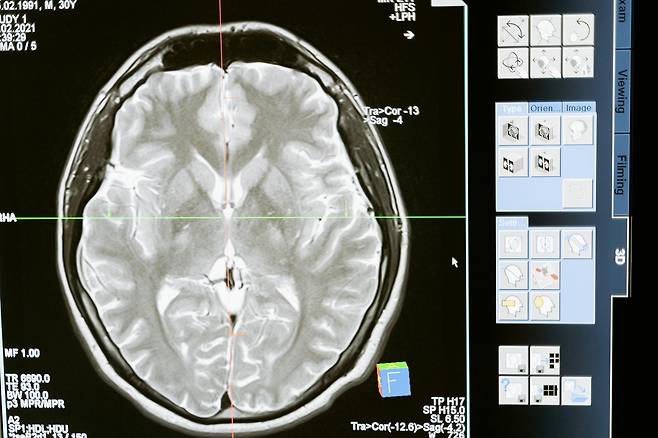

체온보다 훨씬 높은 물로 샤워할 경우, 몸은 급격한 혈관 확장에 반응하게 됩니다.

이때 심장은 더 많은 피를 보내기 위해 빨리 뛰고, 뇌혈관에는 강한 압력이 가해집니다.

특히, 평소 고혈압이나 당뇨를 앓고 있는 사람, 혈관 탄력성이 떨어진 중장년층은이 자극으로 인해 뇌출혈이나 실신 위험이 커질 수 있습니다.

이러한 급격한 혈압 변화는 뇌졸중이나 미세 출혈의 원인이 될 수 있어한 번의 샤워가 평생의 건강을 바꿀 수 있습니다.